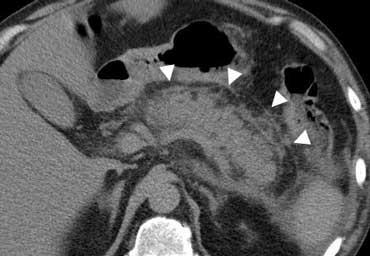

Viêm vùng chậu

Viêm vùng chậu là bệnh lý thường hay bị nhầm lẫn với cả viêm ruột thừa lẫn viêm túi thừa.

Siêu âm qua đường âm đạo cho thấy buồng trứng viêm to không đồng nhất.